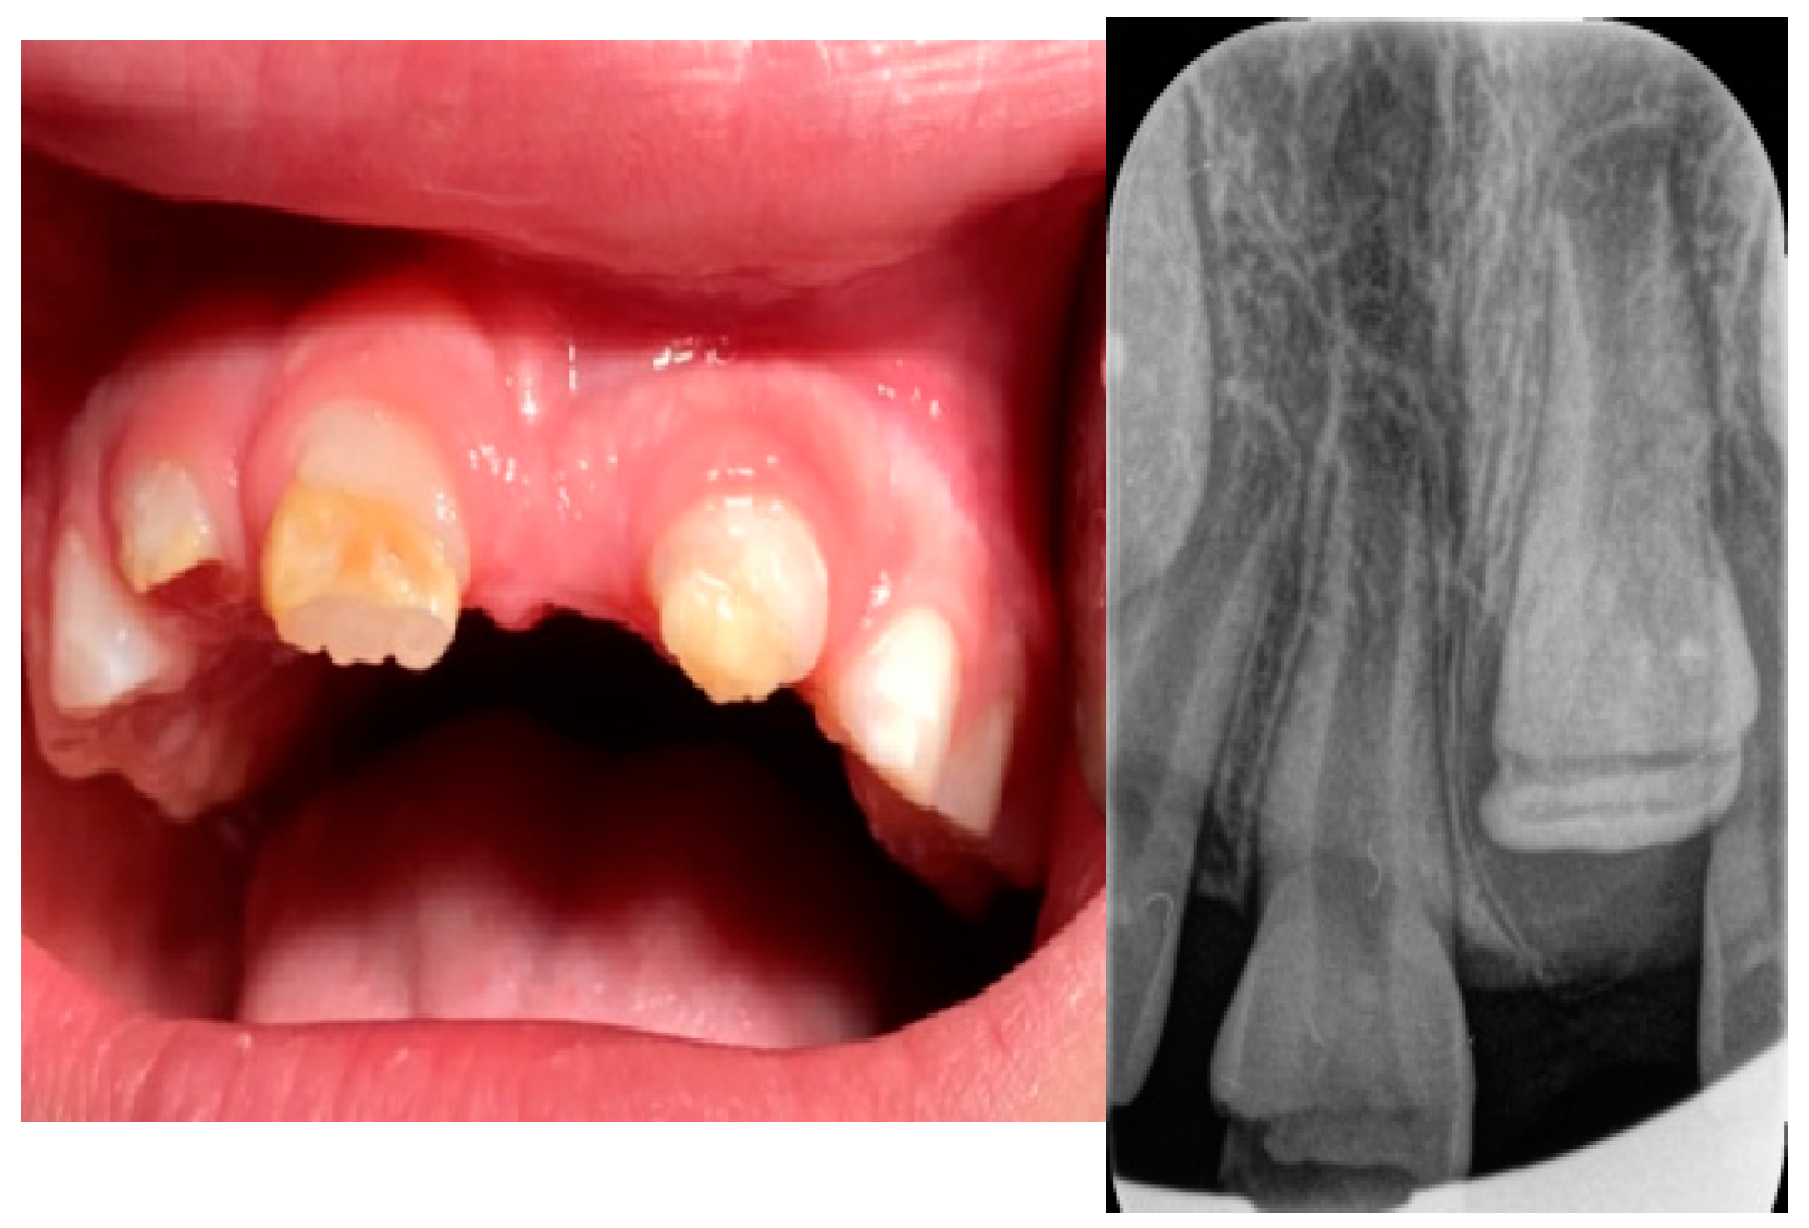

2. Case Presentation